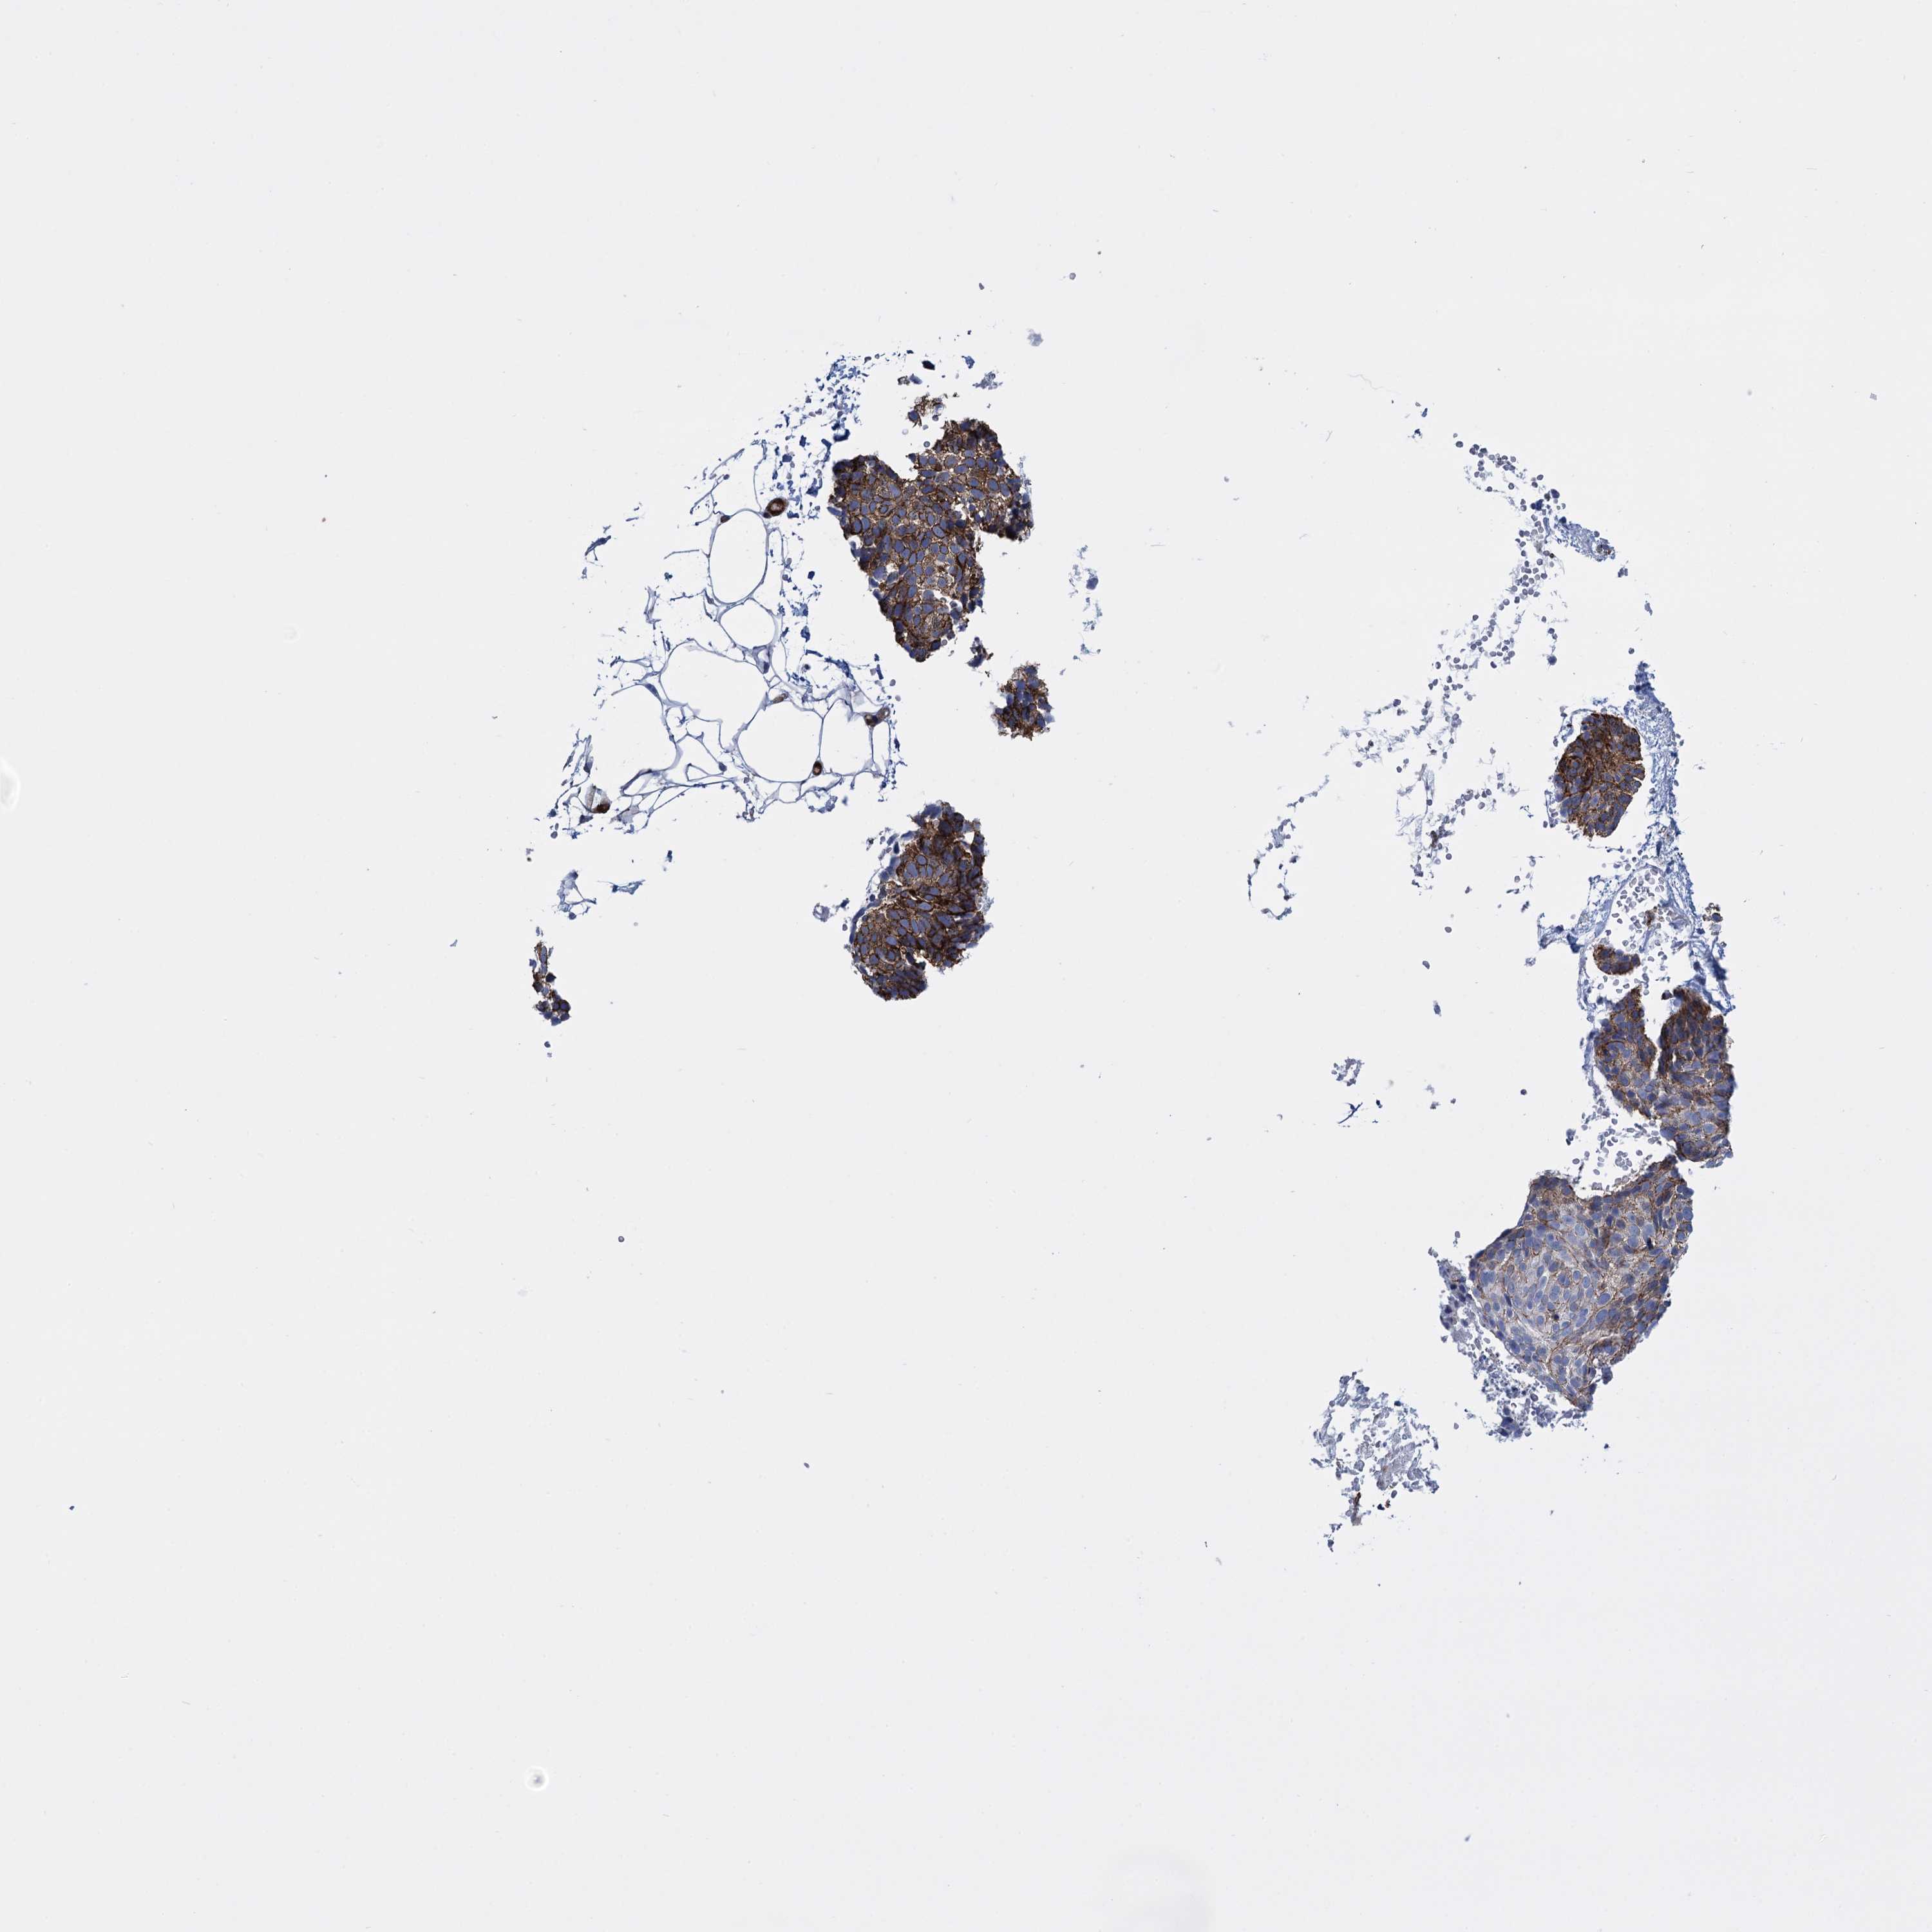

SKIN CANCER - Protein expressioni

A mouse-over function shows sample information and annotation data. Click on an image to view it in a full screen mode. Samples can be filtered based on level of antibody staining by selecting one or several of the following categories: high, medium, low and not detected. The assay and annotation is described here.

Each image is clickable and will lead to virtual microscopy that enables deeper exploration of all samples and also displays staining intensity scores, fraction scores and subcellular localization as well as patient and tissue information for each sample.

Antibody CAB001452

Basal cell carcinoma